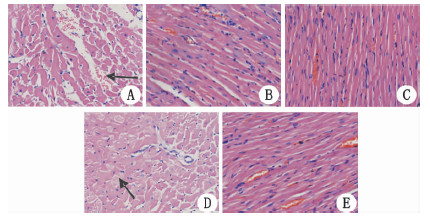

2.1 HE染色结果4 h时HE染色图片两组均可见心肌细胞肿胀、充血,部分细胞坏死、肌溶解,其中窒息组充血肿胀更明显,而室颤组较窒息组肌溶解更明显;72 h实验组肌纤维对比假手术组增粗,心肌排列紊乱、疏松,并有少许炎症细胞浸润。见图 1。

| A:窒息组4 h(箭头示心肌细胞充血肿胀);B:窒息组72 h;C:假手术组;D:室颤组4 h(箭头示肌溶解);E:室颤组72 h 图 1 各组心肌HE染色图片(×200) Fig 1 HE stains of myocardium in each group (×200) |

3 讨论 3.1 复苏后早期不同模型心脏损伤和功能变化本研究心肌组织HE染色图片可观察到4 h时室颤及窒息模型都有心肌损伤,室颤组肌溶解明显。线粒体是细胞能量代谢的场所,再灌注期线粒体氧化磷酸化功能异常,产生大量活性氧,损伤线粒体呼吸链结构,使线粒体氧化磷酸化功能下降[2, 10]。RCR初步提示线粒体呼吸功能,从能量代谢能力方面评价心肌损伤及修复情况,两种模型RCR显示心肌线粒体呼吸功能受损。与此类似,心脏彩超提示两组的心脏左室射血分数下降,以上均提示在复苏后早期两种复苏模型的心肌损伤严重,心功能下降。这与Tang等[4]等发现大鼠复苏后心肌的收缩功能和左室顺应性下降,Gazmuri等[5]发现猪复苏后左室射血分数下降,每搏输出量和心脏做功指数下降,所提示的心肺复苏后早期即出现严重心功能不全的结果相符。然而Wu等[9]在猪8 min心搏骤停窒息法和室颤法复苏模型的比较中提出,在复苏后早期窒息模型心肌超微结构损害及凋亡较室颤模型严重;Tsai等[7]在大鼠5 min心搏骤停复苏模型的对比中亦提出在复苏后早期窒息模型出现弥漫性心肌损伤;而本研究心脏彩超结果却显示,复苏后早期室颤模型心功能较窒息模型差(EF减小)。考虑与室颤模型在电流刺激下发生严重的心电紊乱导致心搏骤停和心脏供血的突然中断,在再灌注时期可能发生心肌顿抑[11]有关,心肌顿抑虽然无心肌坏死,但在心脏血流恢复之后心功能障碍却无法立即恢复[11],导致暂时性的心功能恶化。